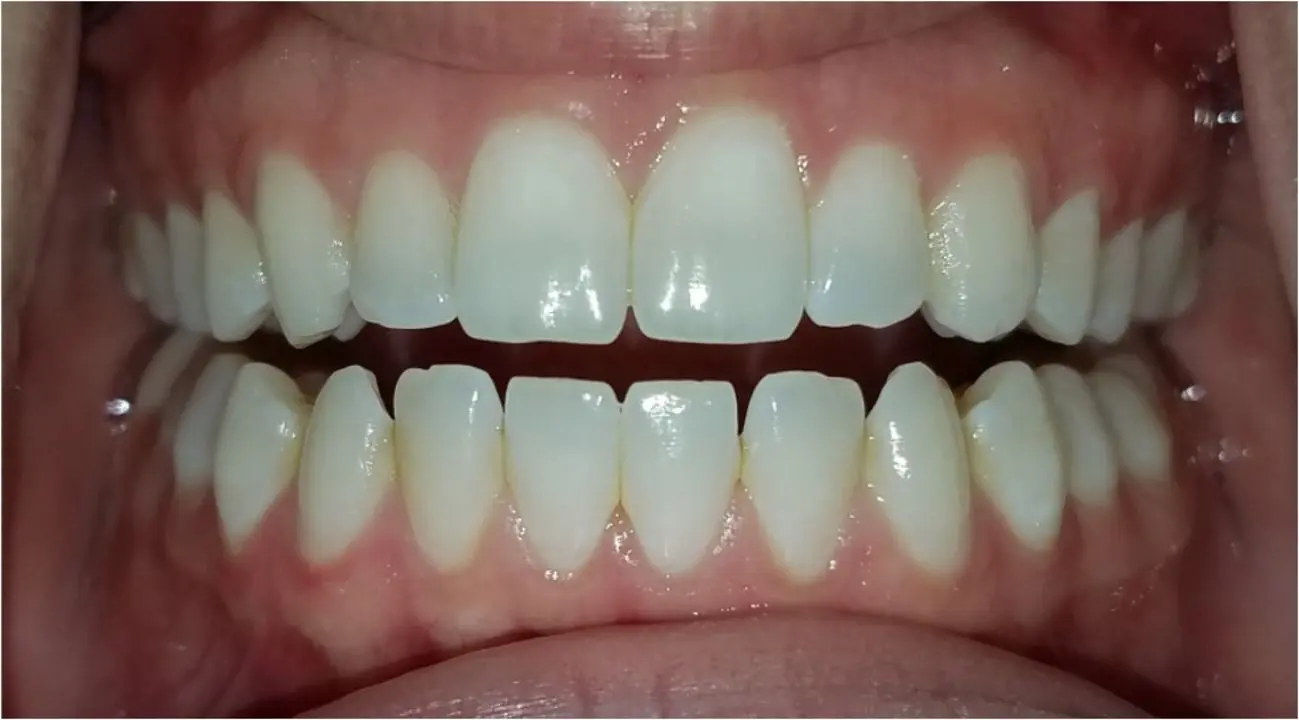

ارتوسرجی یا ارتودنسی همراه با جراحی فک یک روش درمانی است که برای اصلاح مشکلات فکی و دندانی جدی مورد استفاده قرار میگیرد. در این روش، ابتدا ارتودنسی برای تنظیم دندانها و آمادهسازی آنها انجام میشود، سپس جراحی فک برای اصلاح ساختار فک و بهبود عملکرد آن صورت میگیرد. این درمان میتواند مشکلاتی مانند فک جلو، فک عقب، عدم تقارن صورت، بروکسیسم و مشکلات تنفسی را اصلاح کند.

✔ بهبود عملکرد جویدن و تکلم

✔ اصلاح ناهنجاریهای شدید فکی

✔ بهبود زیبایی چهره و افزایش اعتمادبهنفس